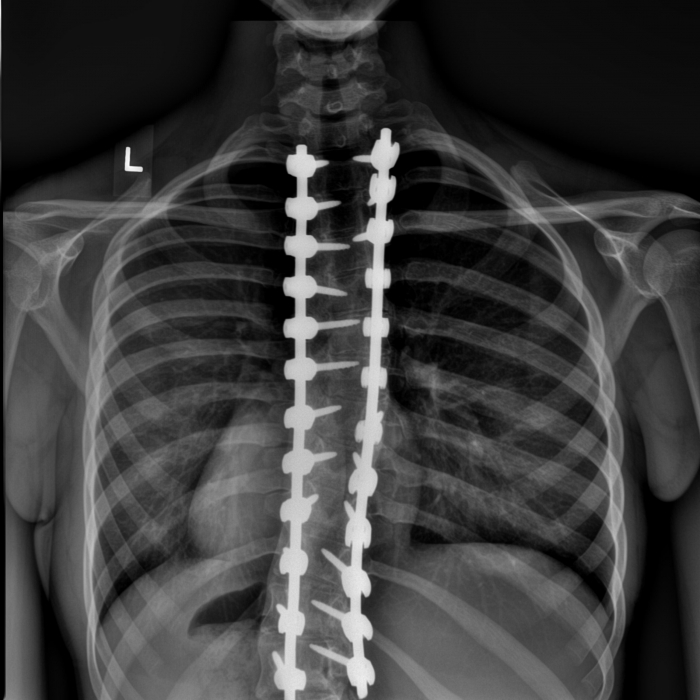

Surgeons assess the patient and their X-rays, CT or MRI scans. Scoliosis surgery often involves fusing the bones of the spine or rods might be inserted to hold the spine straight. New approaches such as tethering also may be an option.